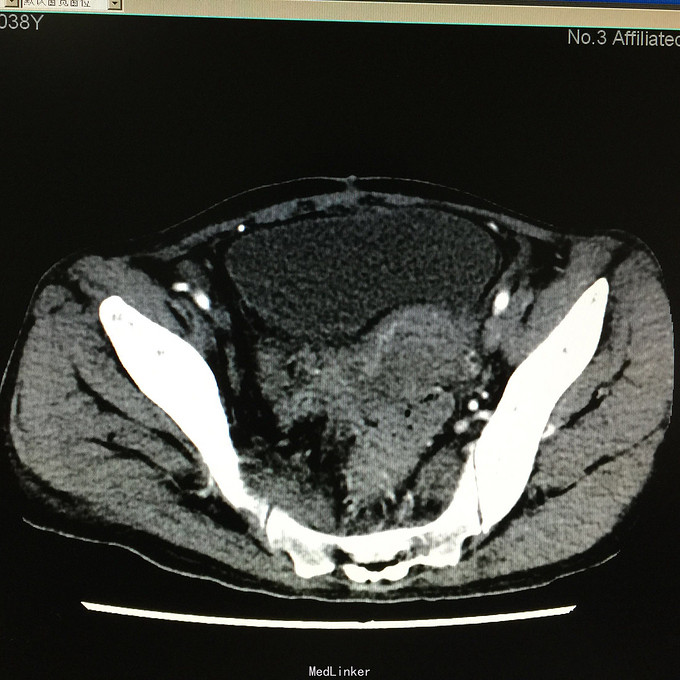

查体无特殊。 辅助检查:中下腹CT平扫+增强+CTU+CTA示:1.右输尿管中上段病变,考虑恶性病变,周围多发淋巴结转移,髂总动脉及髂外动脉起始部、髂内动脉中上段受侵闭塞,右侧腰大肌可疑受侵;建议输尿管镜检查;右肾重度积水,右肾功能明显受损。2.CTA示:右肾动脉纤细,肝右动脉起源于肠系膜上动脉。3.子宫体密度不均匀,建议MRI检查。中下腹MRI平扫+增强+MRU检查结果类似。

患者术后2月出现反复臀部疼痛,左侧为主,疼痛跑迷宫为隐痛,于翻身及活动时加重,卧床休息可稍缓解,多于下午出现,伴有发热,最高达39℃,在当地医院予“氟康唑”及止痛治疗后稍有缓解,但仍反复发热。后疼痛加剧,并出现双下肢疼痛,以大腿外侧为主,无间歇性跛行,无小腿及双足麻木疼痛不适,行对症治疗后效果不佳,于2015-10-9再次返院,予消炎止痛、营养支持及营养神经等治疗。查CT及MRI均提示骶髂关节炎症及腹膜后巨大病变,右侧髂总动脉及髂内、外动脉上段、右侧腰大肌受累。2015-10-15 14:00患者出现右下肢剧烈疼痛、右下肢乏力和麻木,随后出现2次血便,每次量约100ml,暗红色,无腹胀、腹痛等不适,查血提示白细胞 28.17*10E9/L,中性粒绝对值 25.33*10E9/L,血红蛋白56g/L,予止血、输血、抗真菌、止痛等治疗。19:00再次出现右下肢剧烈疼痛伴右下腹痛,查体:BP 80-90/50-60mmHg,P 100-106次/分,R 23次/分,SpO2 100%。右下腹轻压痛,反跳痛阴性,右下肢蹲背伸及踝背伸肌力II-III级,立即行全腹CT检查,示右髂总动脉假性动脉瘤破裂,予加强输注浓缩红细胞及补液支持治疗。清介入科会诊,考虑脓肿和感染为介入血管腔内支架置入治疗的禁忌症,建议予血管外科行开放手术,予患者及家属沟通,并转外院血管外科进一步治疗。